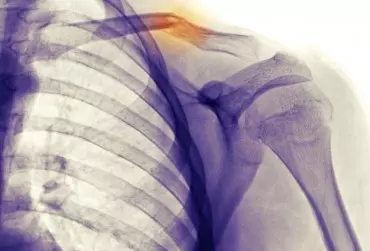

Postępowanie fizjoterapeutyczne po złamaniu obojczyka

Złamania obojczyka stanowią ok. 2–5% wszystkich złamań oraz ok. 40–60% wszystkich złamań w okolicy obręczy barkowej. Większość obrażeń obojczyka występuje na skutek bezpośredniego urazu okolicy barku.

Postępowanie rehabilitacyjne w schorzeniach stawu barkowo-obojczykowego – od diagnozy do terapii

Dolegliwości w kompleksie barkowym to coraz częściej występujący problem. Bark umożliwia różne położenia i konfiguracje kończyny górnej, dlatego jego schorzenia wpływają tak negatywnie na codzienne aktywności całego organizmu. Lekceważenie zmian może skutkować poważnymi oraz nieodwracalnymi uszkodzeniami aparatu ruchu. Chociaż zmian różnicujących bóle barku jest wiele, istotne staje się wprowadzenie fachowej diagnostyki determinującej pożyteczne leczenie.